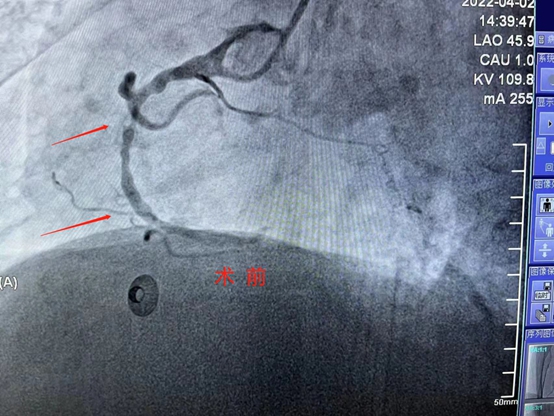

近日,商城县人民医院心血管内科首次开展血管内超声检查(IVUS)加血管内旋磨技术,这一手术治疗的完成,实现了商城县心血管疾病治疗新的突破,真正做到了大病不出县,在家门口就能享受三甲医院的治疗水平,很大程度的缓解了看病远、看病难的实际问题,造福了大别山区广大心血管疾病患者。 患者刘某,女,72岁,因有发作性胸闷、胸痛1月余并且加重3天来我院心血管内科就诊,入院后阳性检查结果示:窦心心率、频发性室性早搏、部分导联ST-T异常、左心房增大、左室壁节段性运动异常、主动脉瓣大量反流,主动脉瓣退行性变,二尖瓣少量反流,左室舒张功能减低;冠脉造影结果示:右冠状动脉重度钙化。经心血管内科熊晨晖主任团队综合评估认为常规的手术方法冠脉支架难以通过和释放,结合患者情况,经与家属沟通后,决定为其行"血管内超声+冠脉旋磨术"。 4月9日,在郑州大学第一附属医院禹海文教授的指导下,心血管内科团队成功为患者右冠脉重度钙化病变处进行了血管内超声+冠脉旋磨术后成功为患者植入了支架,手术过程顺利,术后冠脉血流恢复良好,效果满意,得到了患者及家属的赞扬与肯定! 作为国家标准化心血管诊疗中心,在这两项技术的支持下,我院心血管内科冠脉介入手术将会更加科学化、精准化,进一步提高手术成功率,全面提高我县冠脉介入水平,为复杂冠状动脉病变的患者带来福音,为全面贯彻落实《健康中国行动(2019-2030)》战略,为健康商城贡献一份力量。 科普小知识 血管内超声(intravenous ultrasound,IVUS)是指无创性的超声技术和有创性的导管技术相结合,使用末端连接有超声探针的特殊导管进行的医学成像技术。血管内超声是通过心导管将微型化的超声换能器置入心血管腔内,显示心血管断面形态和(或)血流图形,主要包括超声显像技术和多普勒血流测定两方面。这种技术使得超声技术,如压电传导或者超声传感器得以用于检查血管内壁的情况。 血管内超声主要应用于冠状动脉系统的诊断。1.冠状动脉造影不能明确诊断的病例。2.需明确病变形态和斑块性质。3.评价病变长度,明确支架的选择和放置。4.评价支架植入术等冠状动脉介入治疗疗效。5.冠状动脉病变的远期随访性研究。 什么是冠脉旋磨术? 冠状动脉内膜旋磨术(coronary trartsluminal rotational atherectomy,Rotablator),或称为冠脉旋磨成形术(简称旋磨术),是指使用带有超高速旋转的转头Rotablator将冠脉内粥样硬化斑块、钙化组织碾磨成极细的微粒,从而将阻塞的血管腔的斑块消除。 冠脉旋磨术的适应症 冠状动脉腔内斑块旋磨术主要适用于解剖学上高危的病变,如钙化的病灶、开口处病灶、球囊难以扩张的病灶和长段血管病灶。从冠脉病变分型来看,这些病变多属C型病变,PTCA功率低且并发症发生率较高,但不少报道显示采用旋磨术治疗早期手术成功率很高,而并发症的发生率却明显减少。 冠脉旋磨术的手术方法 先经股动脉硝插入一根8~10F标准导引管至冠状动脉口,然后经导引管送入旋磨导管,将特制的导丝送过狭窄病变至冠状动脉远端,再沿导丝将钻磨头推送至狭窄病变的近端,开动马达使钻磨头高速旋转并推动其前进直到通过病变,最后关闭马达。钻磨头可后撤至病变近端,重复旋磨直到推送和后撤钻磨头时阻力消失,术后重复造影满意,撤出钻磨头。如结果不满意时,可辅以PTCA,以扩张残余狭窄。